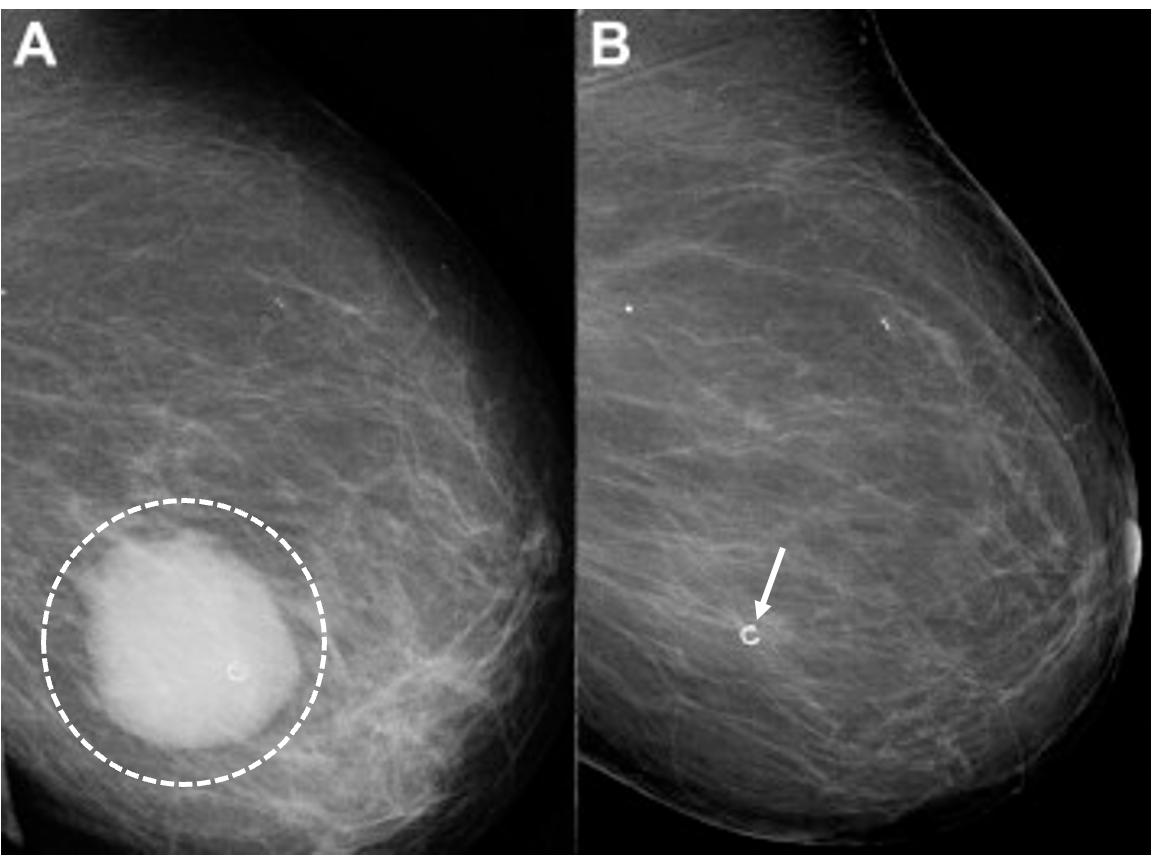

Digital Mammography Breast cancer staging should include bilateral digital diagnostic mammograms (preferably 3D mammograms or tomosynthesis) to evaluate the extent of disease. Although cryoablation is generally performed under ultrasound or CT-scan guidance, high-quality mammography might reveal additional areas of cancer in the same region of the breast (multifocal cancer) or in a different region of the breast (multicentric cancer) that might impact patient selection or alter the cryoablation treatment plan. Multicentric and multifocal breast cancer is generally regarded as a contraindication to cryoablation. Pre-treatment assessment of the mammograms should seek detection of spiculations (radial tumor extensions) and/or microcalcifications that might reach beyond the main tumor mass and require incorporation in the cryoablation treatment zone (Image 1). Since mammography is the only imaging study that reliably shows microcalcifications, mammography plays a particularly important role in determining disease extent when suspicious microcalcifications are part of the disease process. Consequently, patients who are generally opposed to obtaining screening mammograms should be encouraged to have at least one set of pre-treatment diagnostic mammograms to exclude the presence of suspicious microcalcifications that could impact patient selection and/or treatment planning.

Image 1. Mammogram showing density corresponding to a palpable mass (see dashed lines) as well as suspicious microcalcifications (arrows) and inset image showing magnified view of white punctate calcifications extending beyond the palpable mass.